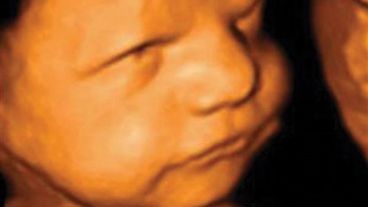

A la vez, veían las reacciones de los fetos utilizando un ultrasonido 4D, lo que les permitió ver que los bebés en desarrollo giraban sus cabezas con mayor frecuencia cuando el estímulo parecía un rostro.